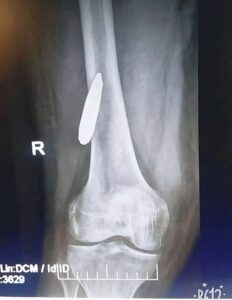

فجأة، كشف الفحص النهائي أن رجل المريض تحتوي بالفعل على رصاصة صامتة منذ حرب 1973، كانت كامنة داخل العضلات طوال هذه السنوات دون أن تسبب أي مشاكل صحية تذكر، حتى ظهرت الآن بسبب ضغط محتمل من أورام البروستاتا.

المريض وزوجته وابنه كانوا مذهولين من الاكتشاف، خصوصًا أنه ظل صامتًا طوال 50 عامًا، ولم يكن يعرف بوجوده، رغم أنه عاش حياته بشكل طبيعي.